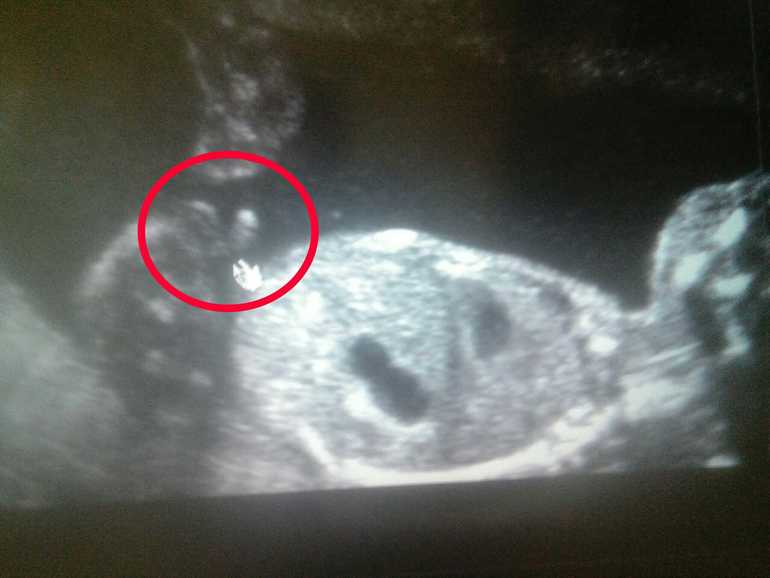

Наш мальчик

Результаты: УЗИ, КТГ, доплера, скринингаСыночек подрос и весит уже 380гр. 21